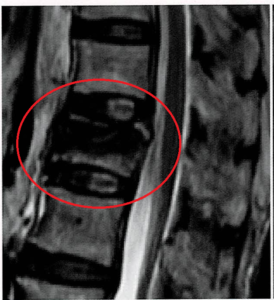

【MRIにおける椎体骨折の見え方】

■基本の見え方

※正常椎体は脂肪髄(黄色骨髄)によってT1WI:高信号(白)、T2WI:中程度(灰色)に見える。

■急性期(~2週間)

・T1WI:低信号(黒)

・T2WI/STIR:強い高信号(白)

⇒骨髄浮腫により水分量増加

⇒骨折線は低信号(黒)で見える場合あり

■亜急性期(~1~2か月)

・T2WI/STIR

浮腫部分⇒高信号(白)

圧潰部分⇒低信号(黒)

正常に治った部分⇒中程度(灰色) ※STIRは低信号(黒)

浮腫が残りまだ治っていない部分、正常に治った部分、圧潰して壊れた部分が混在し、白黒のまだら模様に見える。

■慢性期(数か月~)

・T1WI:高信号(白)~やや低信号(黒)

・T2WI:中程度(灰色)

・STIR:低信号(黒)

⇒浮腫消失、正常な状態へ戻り始める

⇒骨癒合不全で圧潰し、骨構造が破綻してしまった場合は全シーケンス低信号(黒)

■椎体内クレフト(裂け目)

・クレフト内に気体⇒全シーケンスで低信号(真っ黒)

・クレフト内に液体⇒T1WI:低信号(黒)、T2WI/STIRで高信号(白)